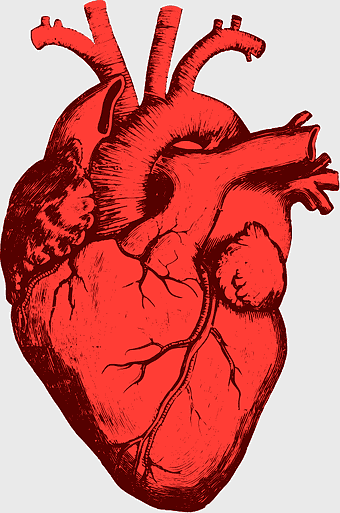

red heart anatomy, human heart drawing, cartoon heart illustration, love and biology, cardiovascular system diagram, medical art depiction, organ structure visualization -

human heart diagram, cardiovascular system anatomy, blood vessel chart, free body diagram, circulatory system illustration, medical organ visualization, human anatomy study -

human heart anatomy, cardiac muscle illustration, circulatory system model, heart health visual, cardiovascular organ diagram, medical heart image, visceral structure depiction -

heart anatomy illustration, cardiovascular system diagram, circulatory system medical, vascular system sonography, human body blood flow, arterial network visualization, heart function analysis -

human heart illustration, cardiac anatomy diagram, heart blood vessels, medical organ visuals, cardiovascular system chart, human anatomy study, circulatory system illustration -

Heart Anatomy Atrium, Aortic arch Human body, human circulatory system, ventricle and heart阀, cardiovascular health, thoracic cavity structures, heart valve functionality, atrium blood flow diagram -